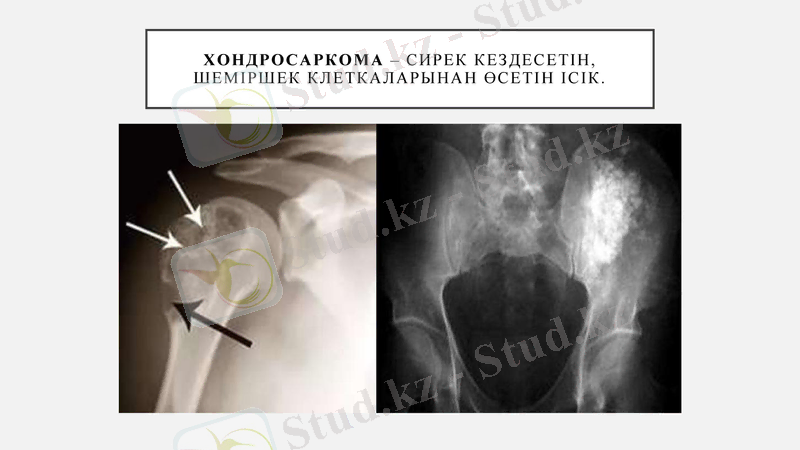

Хондросаркома - сирек кездесетін, шеміршек клеткаларынан өсетін ісік.